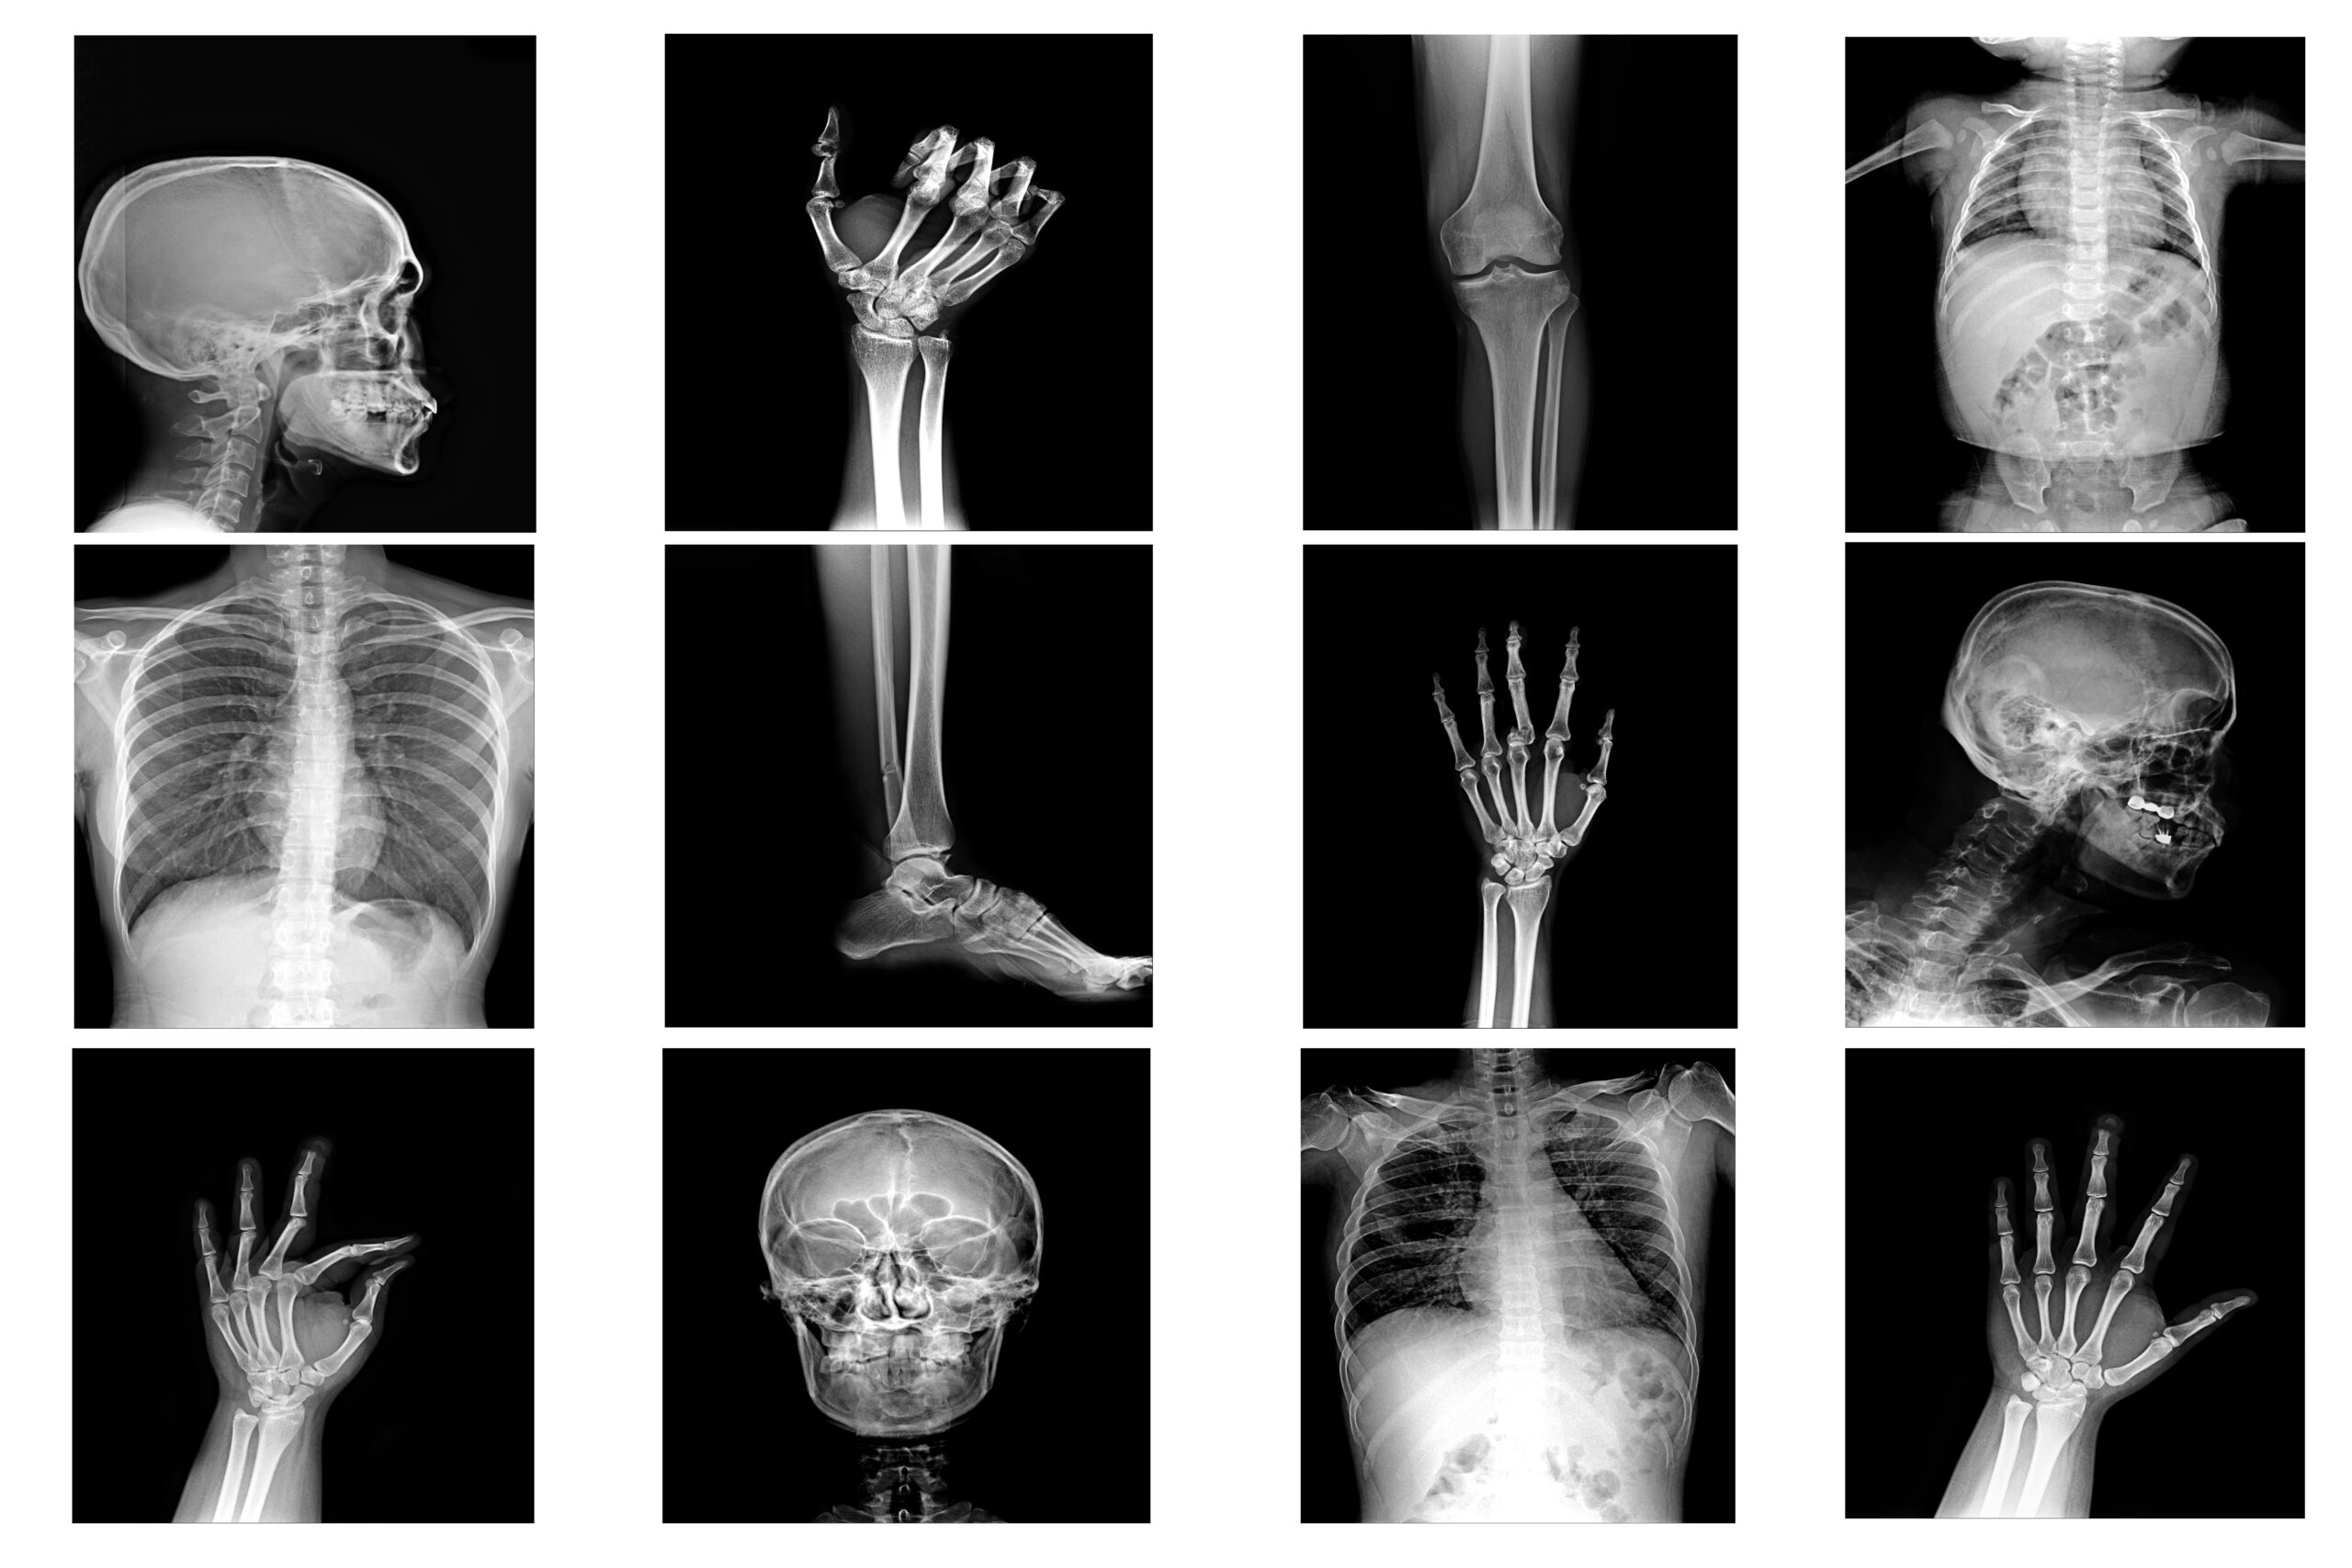

Diagnostic X-Rays – Used for imaging bones and organs (fractures, chest exams, etc.).

Dental X-Rays – For teeth and jaw imaging (bitewing, panoramic).

Mammography X-Rays – Specialized imaging for breast examination.

Fluoroscopy – Real-time moving X-ray images (often used in surgeries).

Interventional X-Rays – Used to guide minimally invasive procedures.